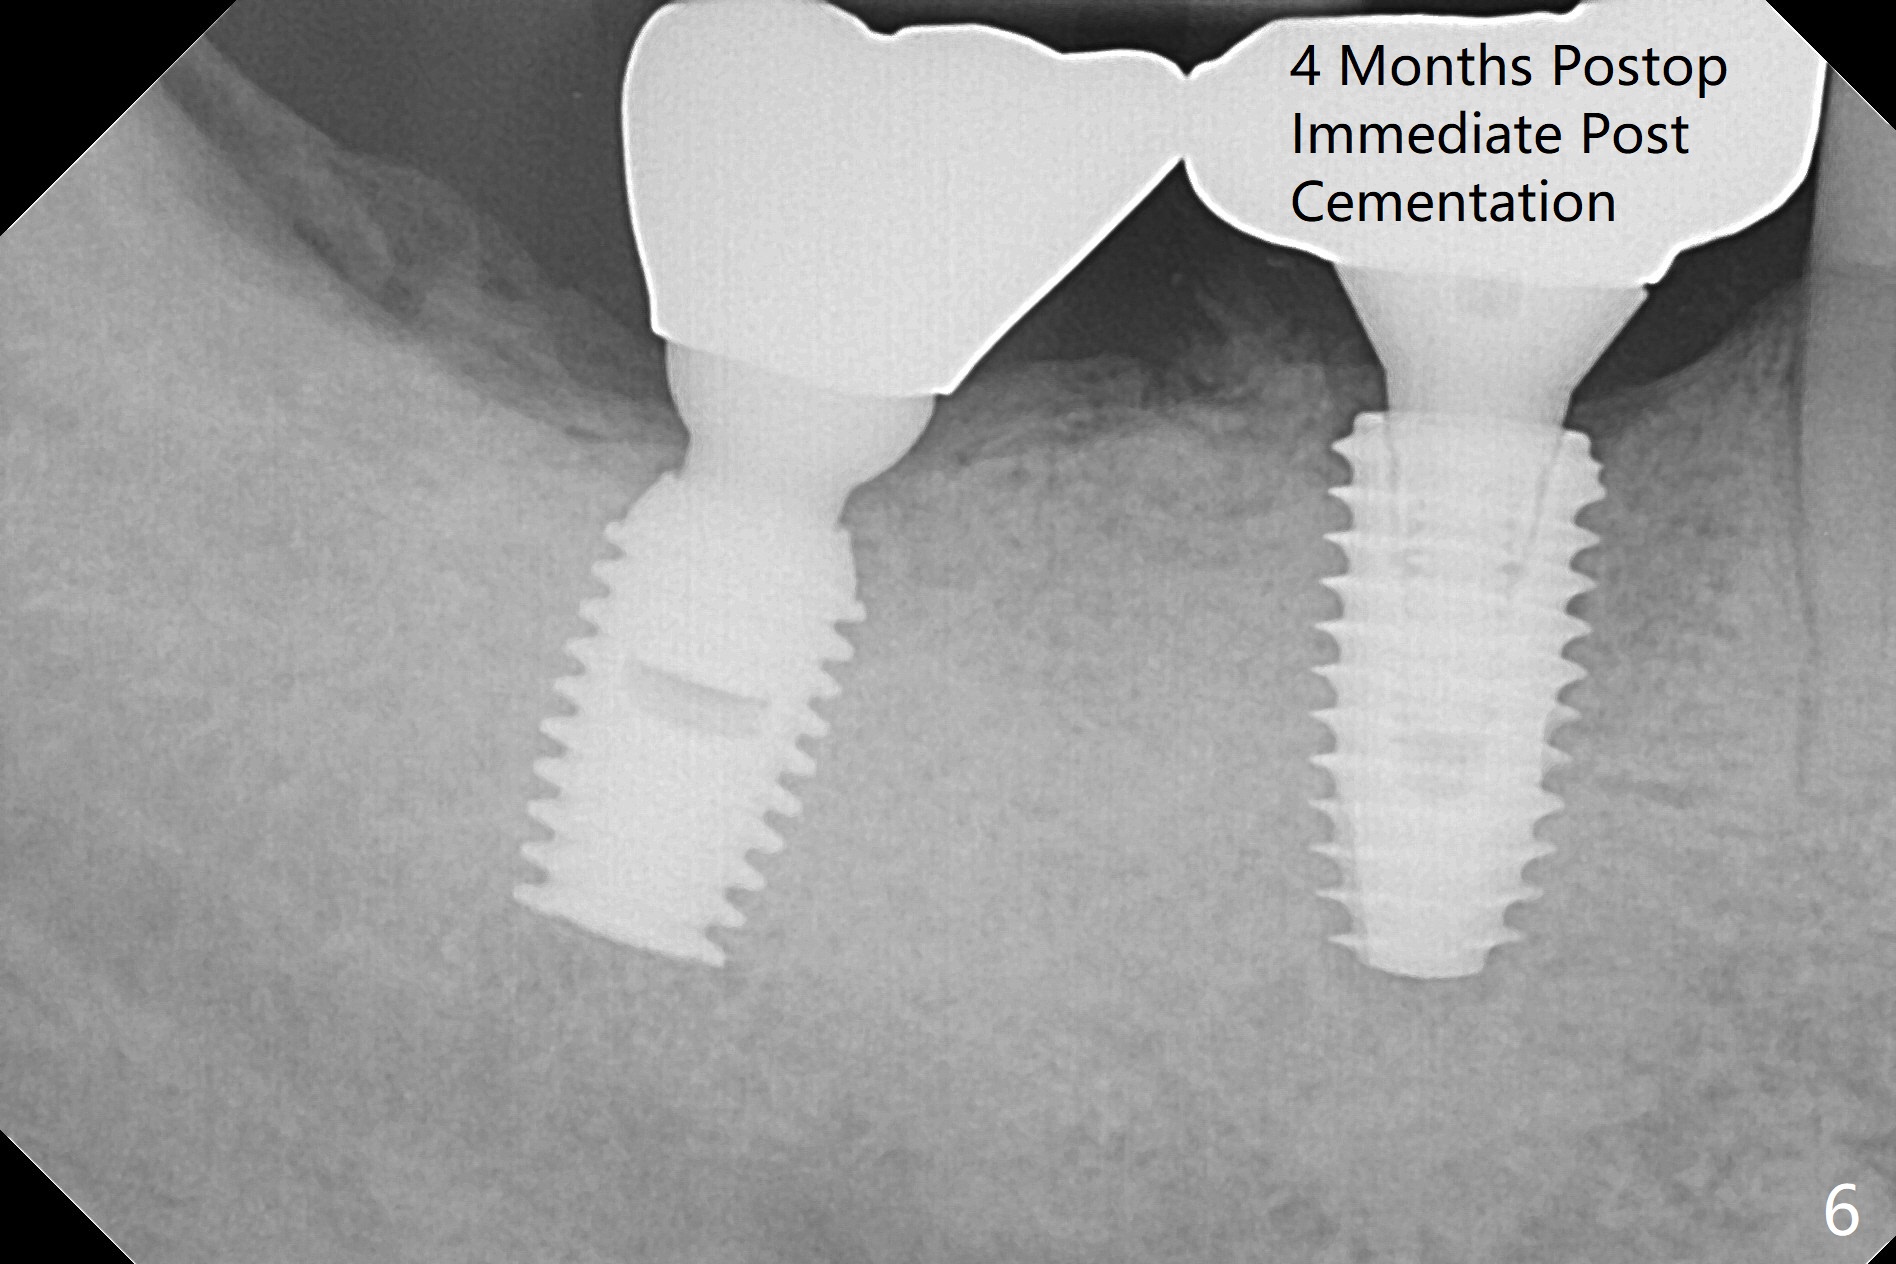

Vertical fracture of the mesial root of the tooth #30 after RCT is associated with bone loss (Fig.00 *). When the mesial portion of the mesial root (M', loose one) is exfoliated, the bone loss resolves (Fig.0). To reduce heat-induced bone necrosis at #19, osteotomy is conducted slowly with copious irrigation with cold saline. Bone density is felt while a 5x10 mm implant is being placed after using cortical tap to the 2nd line of the implant driver. The implant needs to be reverse torqued several times before reaching its final depth (Fig.1 (~50 Ncm)). Since the residual roots are superficially positioned, the immediate implant looks as a delayed one. Although the implant is placed mesial to the septum clinically, its position in X-ray seems to be normal. Because of severe wear and lack of vertical height, a 6.8x5 mm healing abutment is placed. Retention of bone graft (Fig.1 *) is maintained by spreading setting acrylic into the edentulous undercut areas (Fig.2 *). The so called "acrylic dressing" remains in place 3 weeks postop (Fig.8). When it is removed with the healing abutment, the wound heals (Fig.3). Note the limited vertical height. The bone graft placed in the distal socket appears to have been converted to the native bone 3.5 months postop (Fig.4). To reduce severe wear of the natural teeth, the occlusion of the new crown is not heavily decreased (Fig.5). It should be alright considering favorable crown/implant ratio (Fig.6). There is no bone loss 5 months post cementation, although the abutment screw is just retightened (Fig.7). In spite of poor trajectory associated with #18 (Fig.8) and 31 (Fig.7) Bicon implants, the abutments have not been dislodged. For the bruxer, the next implant at #19 with distal root fracture (Fig.8 ^) should be Bicon. The patient complains of food impaction nearly 1 year post cementation. The mesial and distal contacts of #30 crowns are light. When the abutment/crown is removed, there is implant well contamination (food debris). It appears that the previous abutment (5.7x4(2) mm, Fig.6,7) is incompletely seated. When a smaller abutment is placed and torqued at 30 Ncm, it is seated fully (Fig.9 (<: no gap)). New impression is taken. The distal gingival embrasure is larger than the mesial one because of the higher distal crest (Fig.6,7). If there is food impaction distal to the new crown, the distal crestal bone should be removed with lab closure of the embrasure.